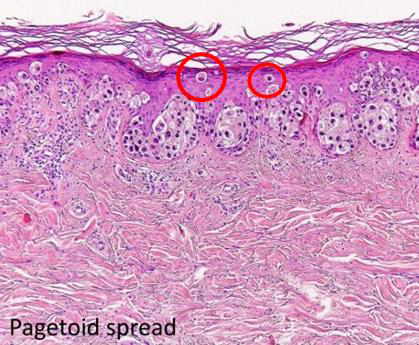

| Superficial Spreading (Pagetoid) - |

|

|

||